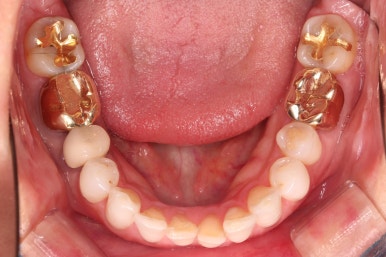

부가적으로 아랫니 앞니가 마모가 심하여 높낮이가 달라보이는 점이었는데요.

아래 앞니는 부분교정까지는 원하지 않으셔서 약간 다듬어 드리고 종료했습니다.